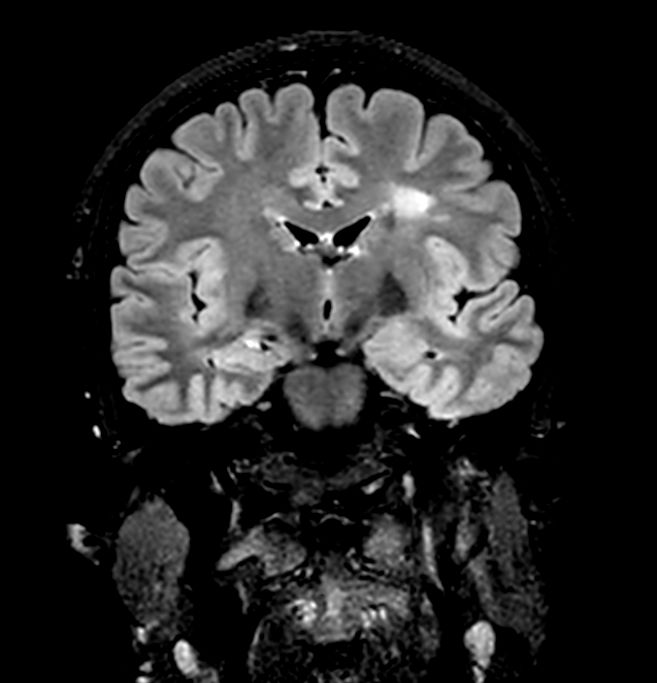

3D VIEW - T2w FLAIR (coronal reformat)

-